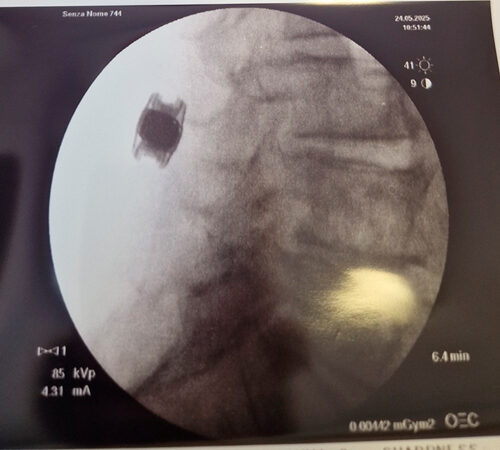

Intervento chirurgico eseguito:

Microdiscectomia cervicale con approccio anteriore + introduzione di cage intersomatica cervicale

Radiografia cervicale post-operatoria